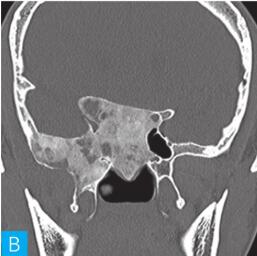

骨纤维异常增殖症:又称骨纤维结构不良,是一种先天非遗传性骨组织疾病,男女均可患病,通常在儿童时期起病,青少年后才出现症状,病程较长。骨纤维异常增殖症特点是病变部位骨质呈膨胀样改变,并累及周围自然孔道、裂隙及软组织,另一特点为跨越颅缝生长并累及多骨。CT图像上受累骨质可表现为囊样、磨玻璃样或硬化样改变。一般以一种类型为主,多种类型并存,相互间可转化。与骨化性纤维瘤相比,骨纤维异常增殖症受累骨质膨胀变形更为明显,且为多骨受累;同时少有骨化性纤维瘤出现的边缘硬化边及骨壳形成。见图2。

图2 骨纤维异常增殖症

A. CT横断面(骨窗);B. CT冠状面(骨窗)